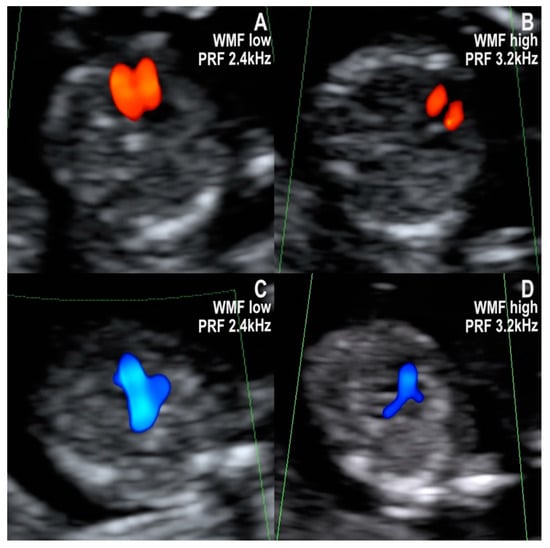

- Normal diastolic filling of both ventricles, with normal cardiac axis and two equally sized great vessels with normal antegrade flow, forming a V sign. This pattern was seen in all of the 20 cases with a structurally normal heart. The pattern’s negative predictive value for CHD that needs major surgical correction after birth is likely high, but little evidence is available to support this hypothesis. Isolated totally anomalous pulmonary veins return, and minor structural defects (e.g., ventricular septal defect, VSD), evolving lesions (e.g., mild valvular stenosis, tumors), or defects that are only postnatally diagnosed (e.g., atrial septal defect, ASD) might show this pattern in the first trimester.

- Common inflow of both ventricles through a common atrioventricular valve and two equally sized great vessels with normal antegrade flow, forming a V sign. All of the atrioventricular septal defect (AVSD) cases in our series showed this pattern in the first trimester. AVSD with situs solitus is usually associated with genetic disorders, namely Down syndrome [16,17].